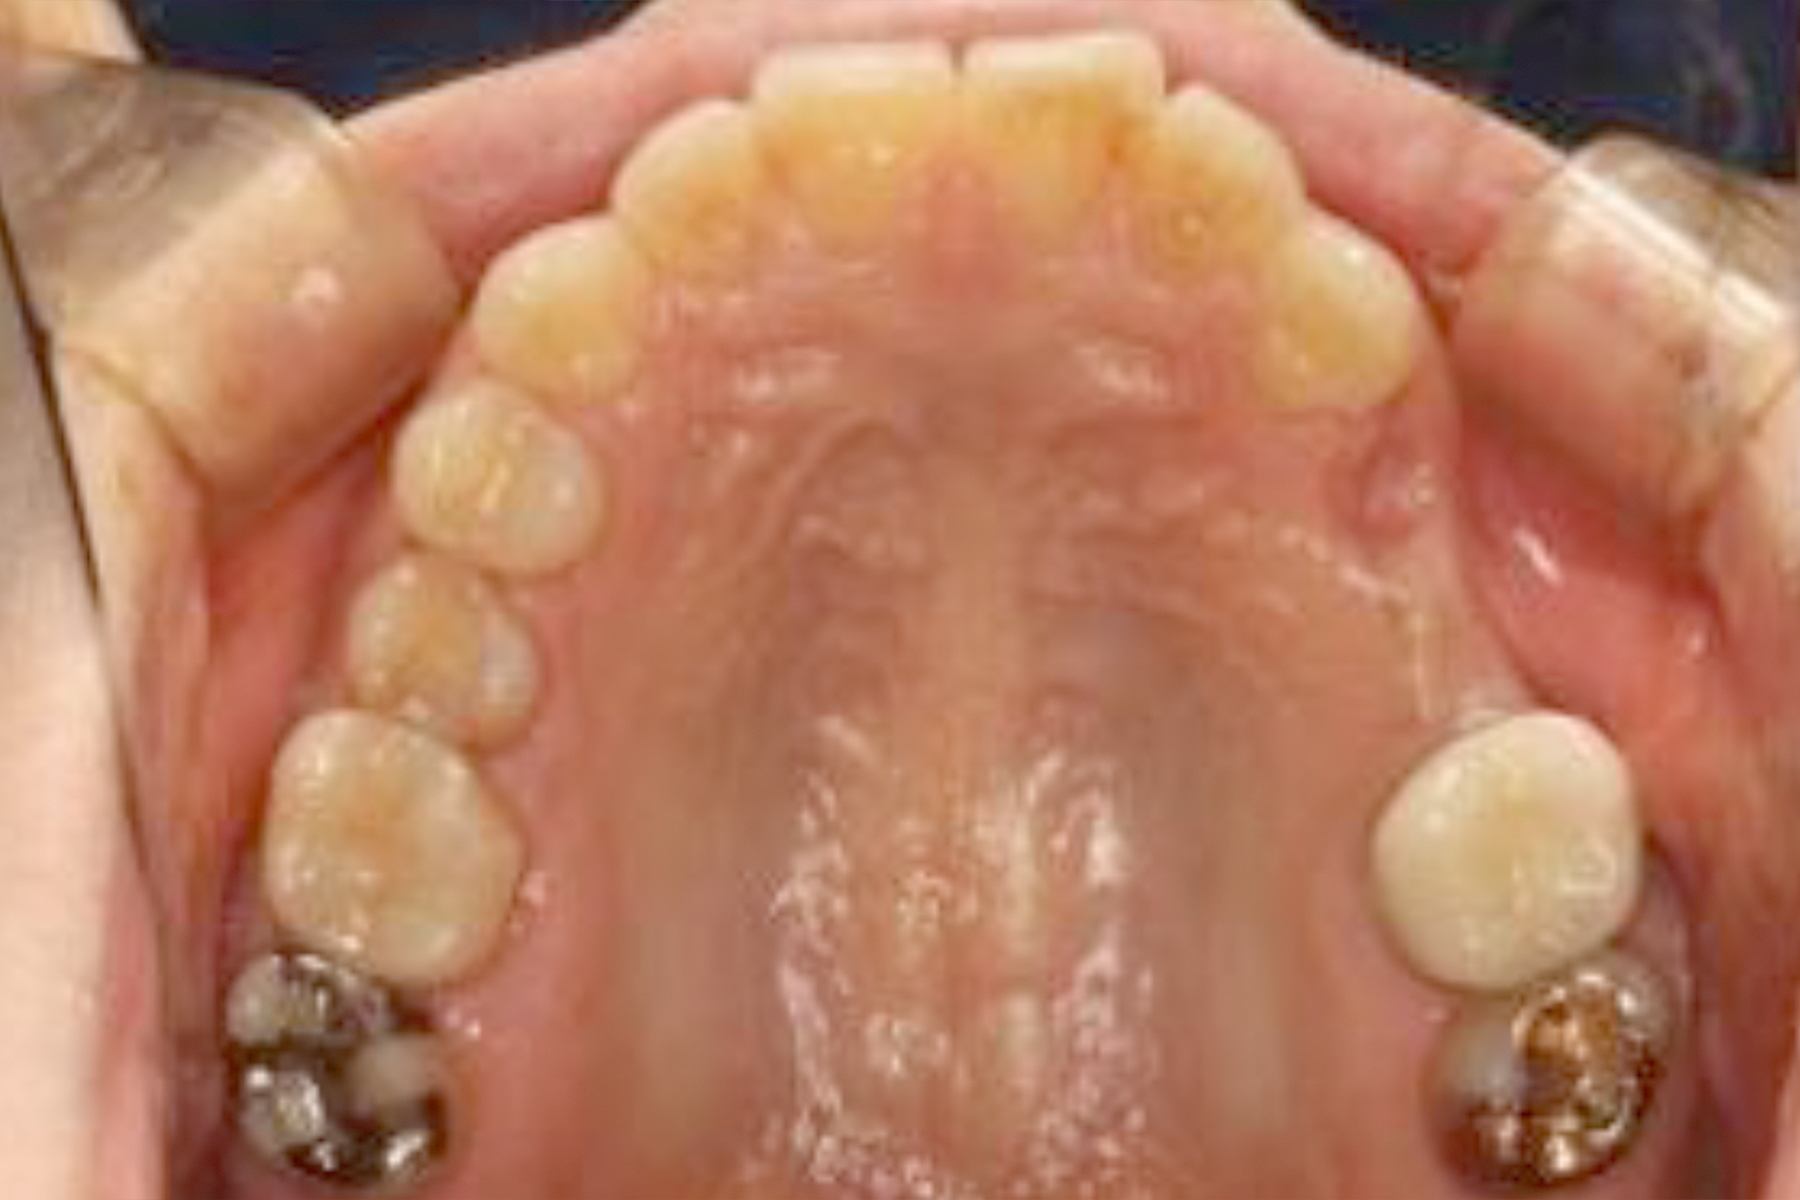

Case.1

BEFORE

| 担当医 | 林 大貴 |

|---|---|

| 主訴 | 左上の歯が噛むと痛い |

| 期間 | 約9ヶ月 |

| 治療内容 | 左上4、5番の欠損部位に対して、人工歯根を埋入し上部構造として補綴物をかぶせた。左上4番についてはインプラント埋入の際にソケットリフトを行った。 |

| 治療に伴うリスク | インプラントは、過剰な咬合力がかかった場合、インプラント周囲炎により骨の吸収を認めることがある。 インプラント周囲炎の可能性があるためメンテナンスが必要。 |